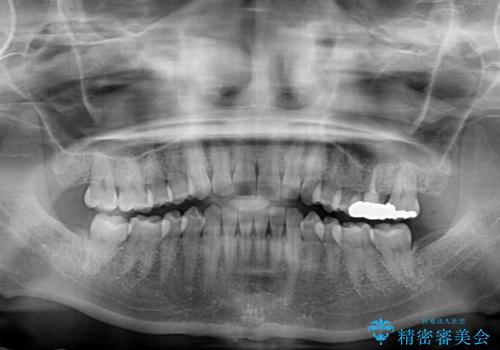

- 奥歯の銀歯をセラミックにしたいとのことで来院された患者様です。

当初は奥歯のみの治療をご希望でしたが、話を進めていくうちに、軽度ではあるものの、幼少期の薬の影響で歯が変色していることがコンプレックスであるということが分かりました。

長年歯の色が塞ぎ込んでいた部分があるとのことで、これを機会に全ての歯を真っ白にするために、オールセラミッククラウンにて補綴治療を行うこととしました。

より白さが目立つように、自然な仕上がりではなく、作り物の雰囲気があるフルジルコニアクラウンにて補綴治療を行いました。